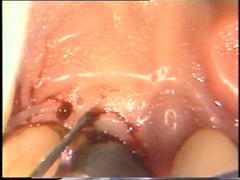

En palatino debe usarse el mismo principio pero la diferencia radica que el tejido palatino es muy fibroso por lo tanto el corte puede realizarse más apical para eliminar la bolsa y poder adaptar mejor el colgajo, que por ser más fibroso es menos flexible que los colgajos bucales. |